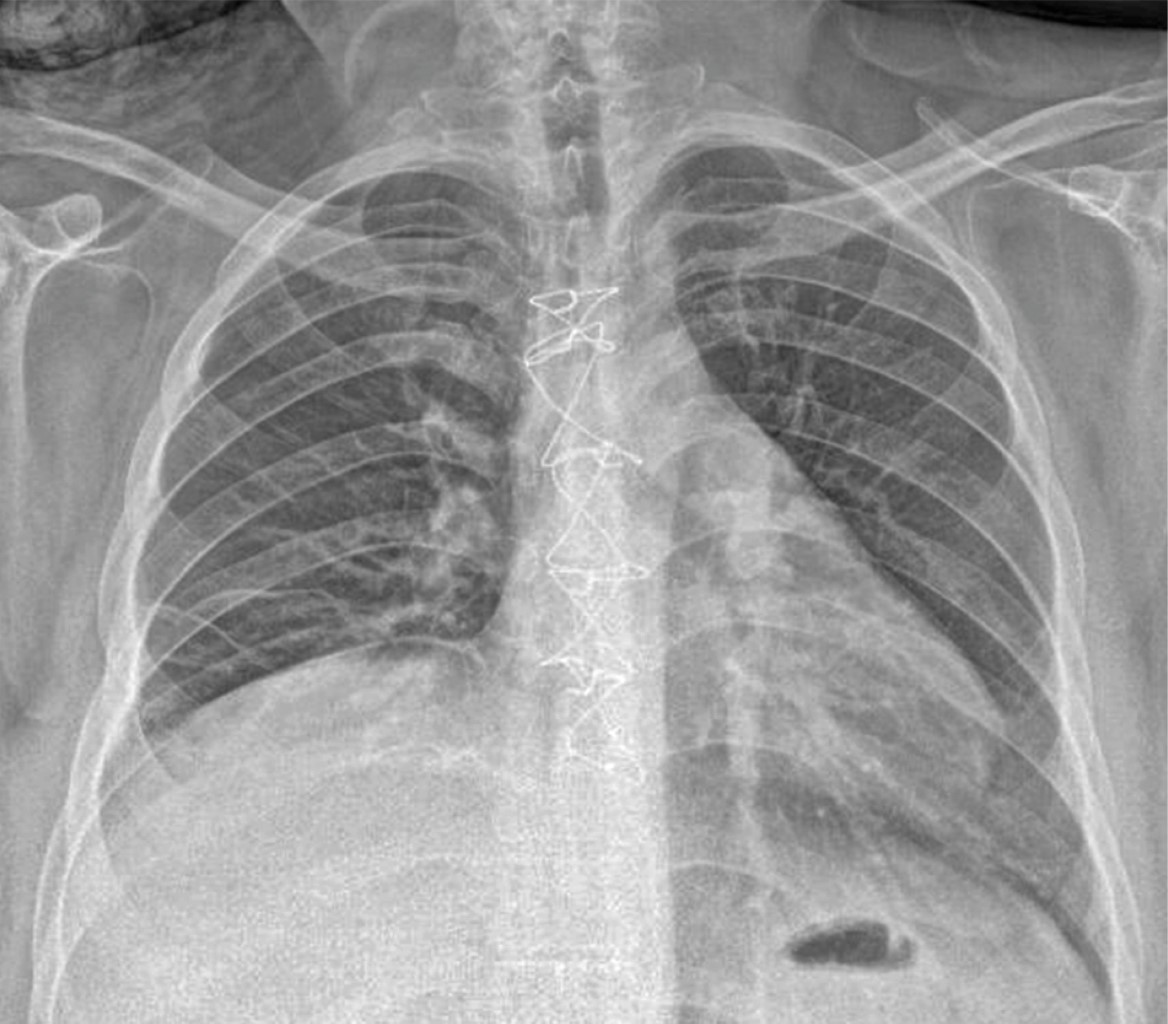

El papel de los estudios de imagen es de vital importancia en el diagnóstico, sin dejar de lado la historia clínica minuciosa y la exploración física. Los principales hallazgos en la radiografía de tórax simple establecen la sospecha de MND junto con los signos y síntomas clínicos de infección severa asociados a la presencia del antecedente de infección cervical, dental u orofaríngea. Dichos hallazgos radiológicos pueden ser: ensanchamiento del mediastino, neumomediastino, niveles hidroaéreos mediastinales, desplazamiento anterior de la columna de aire traqueal por una opacidad prevertebral de los tejidos blandos, agrandamiento de la silueta cardíaca y pérdida de la lordosis normal de la columna cervical así como derrame pleural unilateral o bilateral.9,10,12 De forma inmediata deberá realizarse una tomografía computarizada (TC) cervicotorácica, ya que la TC de tórax y cuello puede revelar información detallada con respecto al alcance del proceso de necrosis, y sugiere, dentro del marco del enfoque de tratamiento quirúrgico, el mejor abordaje para un drenaje efectivo con la finalidad de optimizar el mejor resultado posquirúrgico para el paciente y con ello la necesidad de menos reintervenciones.9,10,13-17

En nuestra serie la radiografía de tórax sigue siendo el estudio inicial en todo paciente con problema respiratorio por su accesibilidad y rápido resultado (Figura 1); sin embargo, la tomografía de tórax sigue siendo el estándar de oro en nuestra institución para el diagnóstico y planeación de manejo quirúrgico en los pacientes con mediastinitis (Figura 2).